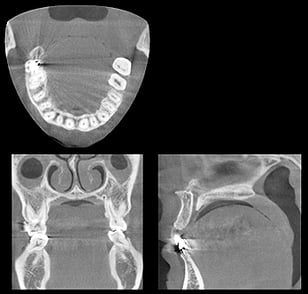

今まで歯科のレントゲン診断は全て平面で情報が得られないため、本来ある病変がレントゲン像では重なって覆い隠されてしまったり、立体的な位置関係がわからないため、限られた情報しか得られませんでした。

歯科用CTの導入により高解像度で立体像が得られるため、今までにない診断が得られるだけでなく、インプラント・矯正治療・精密根管治療・口腔外科手術なども今まで以上に安全に行えるようになりました。

同じCTでも腹部CTなどと違い低被ばくで安心です。